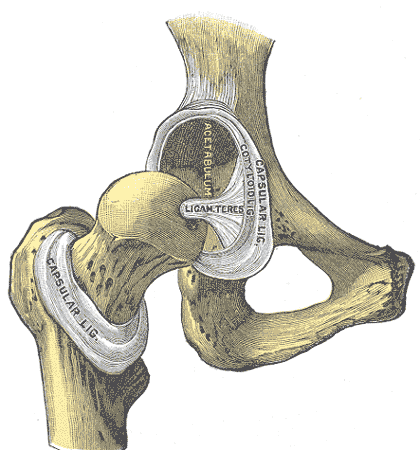

Le relâchement articulaire est la cause principale de la dysplasie de la hanche.

Il est donc primordial de maîtriser la stabilité articulaire et ce, le plus tôt possible.

L’hyperlaxité du ligament rond est la cause sous-jacente de la dysplasie de la hanche chez le chien. Le ligament rond maintient la tête du fémur dans l’acetabulum de la hanche.

C’est lors de la tétée que l’hyperlaxité du ligament rond peut se produire.